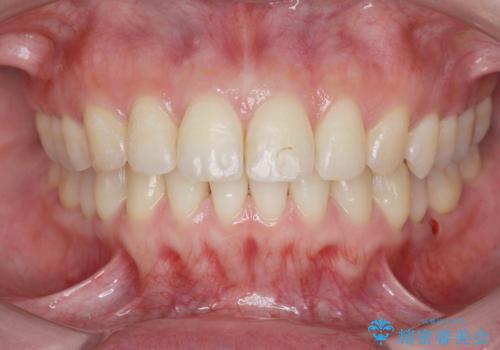

カリエール・マイクロインプラントを併用した歯の突出を改善する大きな遠心移動

- 口が閉じづらく、突出し歯が出っ歯に見えてしまうことの改善を求めて来院されました。

カリエール・マイクロインプラントを用い、時間はかかりましたが大きく歯の後方移動が達成され、前歯の見た目が大きく改善されました。